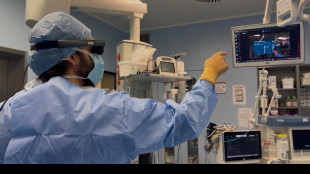

Nella chirurgia maxillo-facciale esordisce il visore di realtà aumentata

La sperimentazione avviata al Policlinico Irccs Sant'Orsola di Bologna